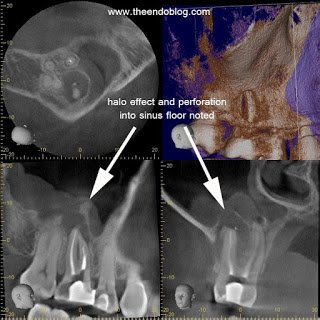

CBCT (J. Morita Veraviewepocs 3De) demonstrates a large periapical radiolucency around the buccal roots of #3. The sagittal and coronal views both show elevation in the floor of the sinus (halo effect) as well as perforation of the floor of the sinus. Endodontic treatment is required BEFORE sinus treatment. Failure to address the odontogenic source of the sinus infection will result in recurrent sinus infections.